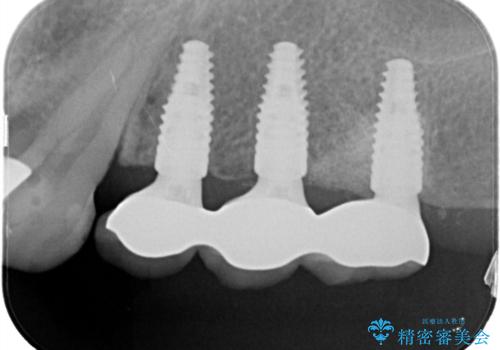

骨増生を行なったのちインプラント埋入を行なっております。